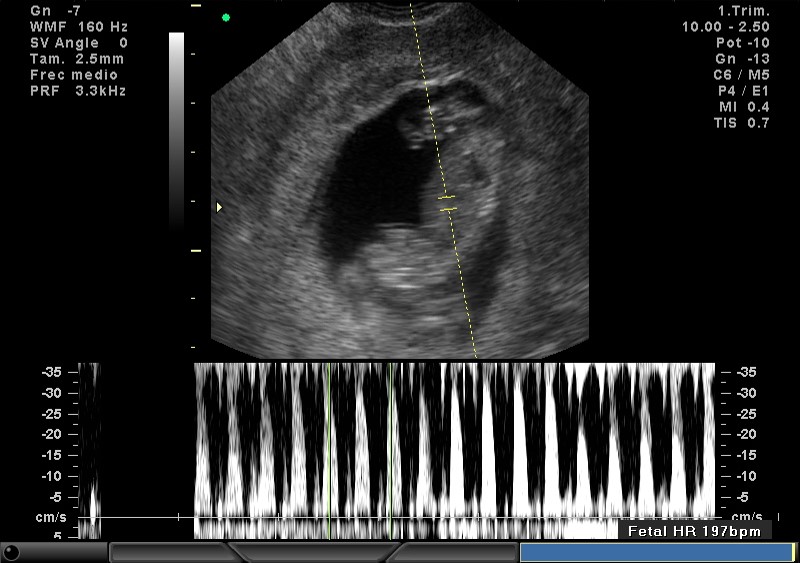

2D FRECUENCIA CARDIACA 10.5 SEMANAS